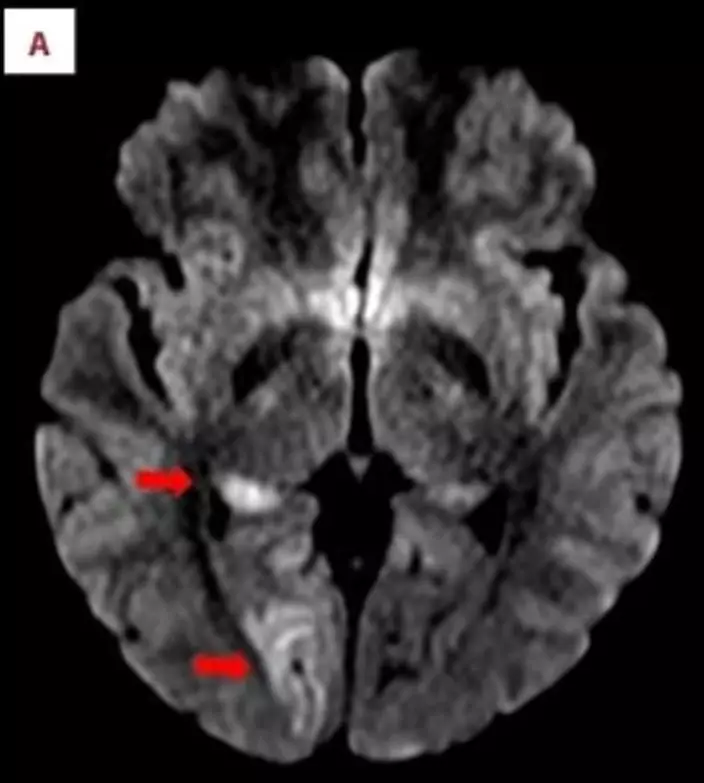

醫生:劇烈動作致動脈撕裂 血栓引發中風

醫療團隊指出,劇烈重複的上舉過肩動作導致患者脆弱左頸動脈撕裂(椎動脈剝離VAD),血液滲入動脈壁形成血栓。該血栓流入腦部阻塞視覺中樞血管引發中風。研究人員雖無法100%確認因果關係,但推測遊戲機械性壓力是中風主因。